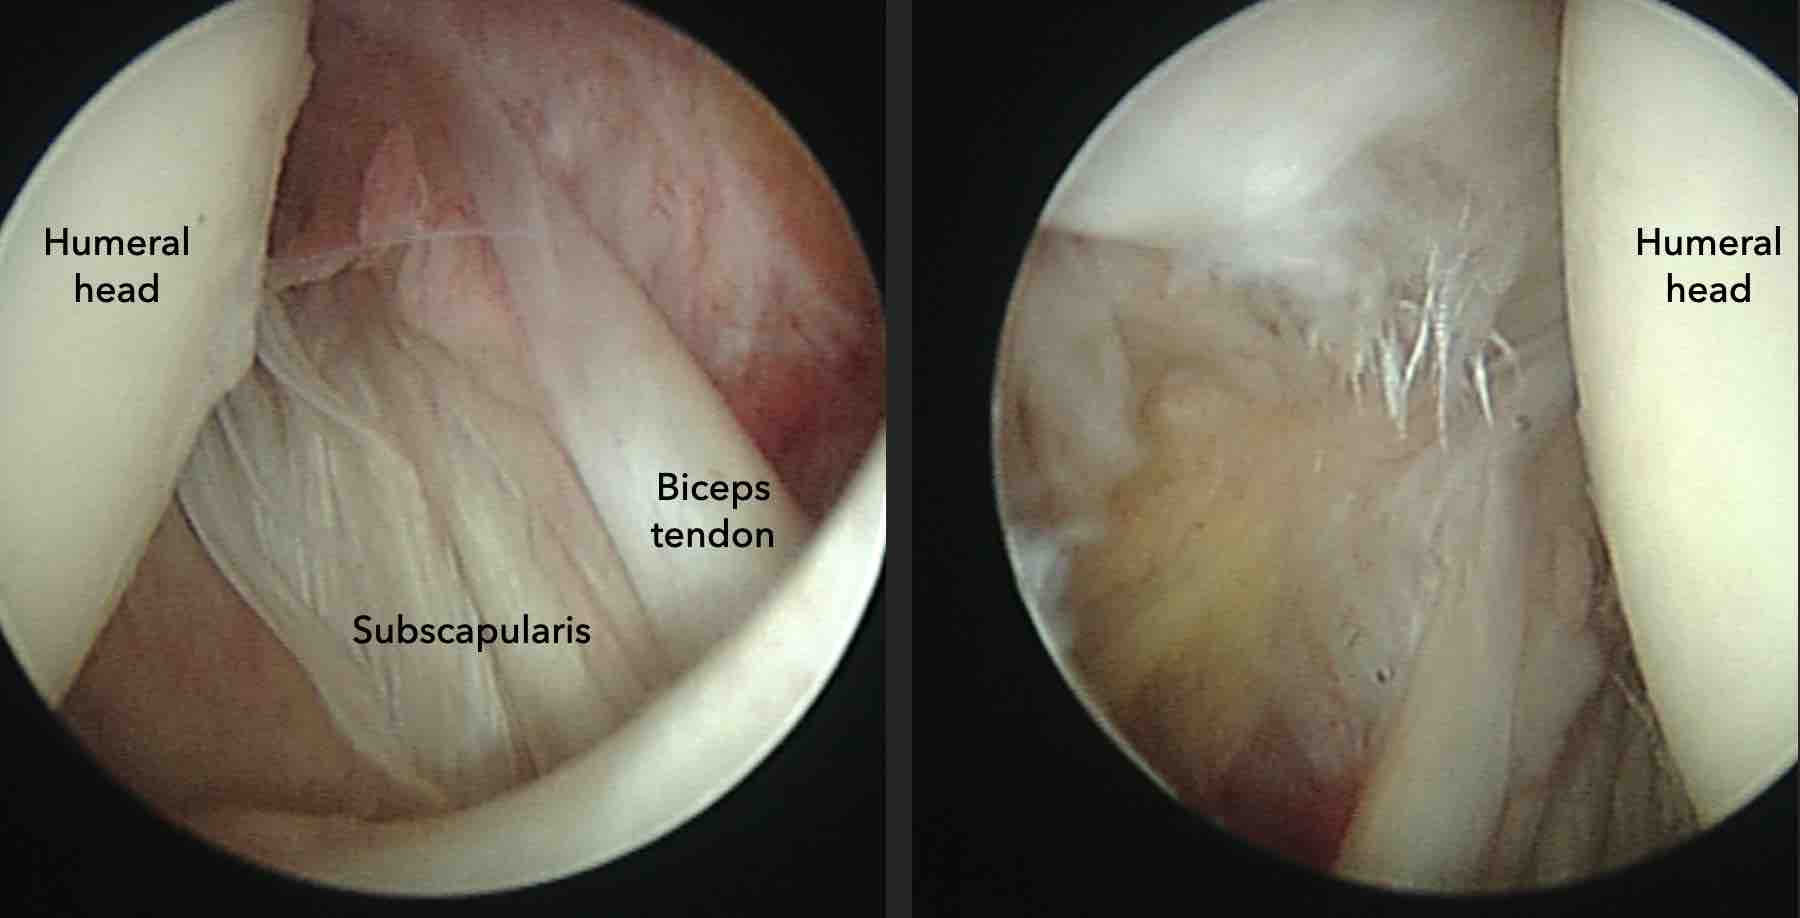

Hình ảnh

Rách gân dưới vai sau chấn thương trực tiếp.

Có hình ảnh co rút gân dưới vai về phía trước kèm phù nề quanh gân trên các chuỗi xung PD-weighted mặt phẳng axial và chuỗi xung T2W xóa mỡ mặt phẳng coronal (dấu hoa thị).

Gân cơ nhị đầu không bị trật (đầu mũi tên).

Bệnh nhân này có tiền sử chấn thương trực tiếp vùng khớp vai phía trước.

Chuỗi xung T2W xóa mỡ mặt phẳng axial và chuỗi xung PD mặt phẳng sagittal chếch.

Có hình ảnh rách không hoàn toàn gân dưới vai kết hợp với phù nề do gãy mấu động nhỏ (lesser tubercle).